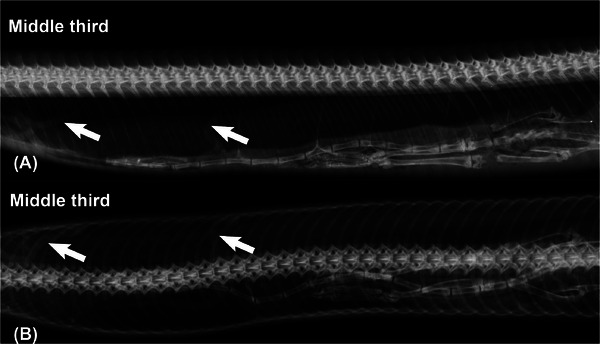

Pentastomids are parasites of the respiratory system of reptiles, birds, and mammals, where they can cause lesions resulting in the death of their intermediate hosts. This report describes radiographic aspects of pulmonary pentastomid infection in the Southern American bushmaster (Lachesis rhombeata). A female juvenile snake rescued in an urban area of the Northeast region of Brazil presented with lethargic behavior. Radiographic examination of the coelom cavity showed long cylindrical structures in the respiratory system with soft tissue radiodensity and width ranging between 4.0 and 5.0 mm. The next day, the snake died and was submitted to necropsy, where lung parasites were discovered, which were later identified as Porocephalus stilesi. A case of correlation between radiographic and macroscopic findings of pentastomid in snakes has not previously been reported.